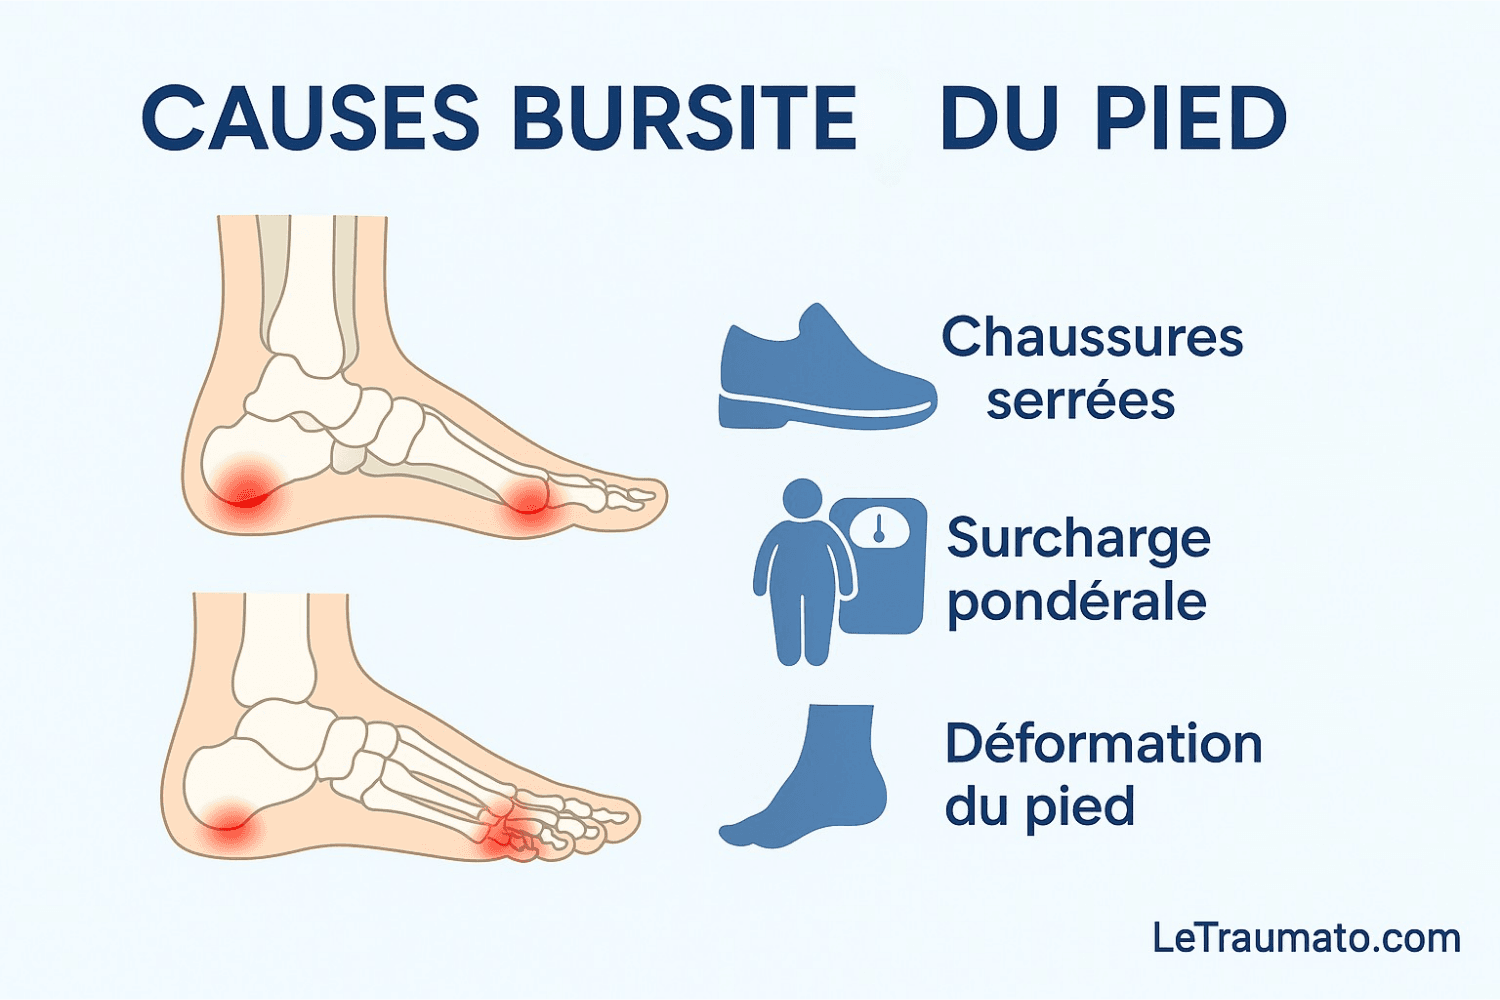

La bursite du pied est une inflammation d’une petite poche remplie de liquide, appelée bourse séreuse, qui joue un rôle d’amortisseur et de protection entre les tendons, les muscles et les os. Quand cette bourse s’enflamme, elle provoque une douleur localisée qui peut devenir handicapante au quotidien.

Chaussures trop serrées ou inadaptées

L’une des causes les plus fréquentes est le port de chaussures étroites ou mal adaptées. Les frottements répétés et la compression mécanique créent une irritation progressive de la bourse, menant à une inflammation douloureuse.

Surcharge mécanique et surpoids

Un excès de poids ou une station debout prolongée augmente la pression sur les articulations du pied. Cette surcharge favorise la compression des bourses séreuses et multiplie le risque de bursite.

Déformations du pied

Les malpositions comme l’hallux valgus déplacent l’appui du pied et créent des zones de frottement. Ces déséquilibres favorisent l’apparition d’une bursite, notamment sur l’avant-pied ou le talon.

Les causes les plus fréquentes sont le port de chaussures trop serrées, la surcharge pondérale, les traumatismes répétés et les déformations du pied comme l’hallux valgus.

Oui. Des chaussures étroites ou rigides entraînent des frottements et une compression des bourses séreuses, favorisant l’inflammation.

Oui. L’hallux valgus et d’autres déformations créent des zones de frottement anormales, augmentant fortement le risque de bursite.

La bursite du pied est une affection douloureuse mais évitable si l’on connaît ses causes principales. Chaussures inadaptées, surcharge mécanique, traumatismes répétés et déformations anatomiques sont les principaux facteurs à surveiller. En adoptant de bonnes habitudes et en consultant un orthopédiste en cas de douleur, il est possible de prévenir cette pathologie et d’éviter les récidives.